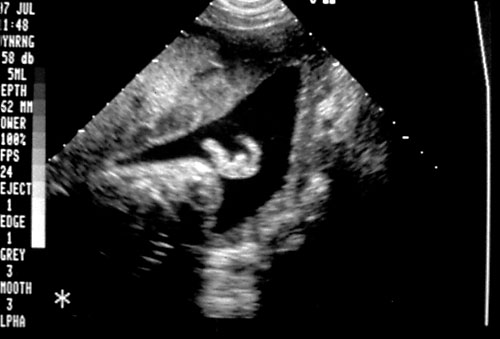

- Breathing movements — 30 seconds of activity.

- Gross body movements — at least three discrete movements.

- Fetal tone — at least one flexion/extension movement.

- Reactive NST.

- Amniotic Fluid Volume — at least one, 2 cm vertical fluid pocket, demonstrable in two anatomic planes.

- Five variables, two points each, score 0-10